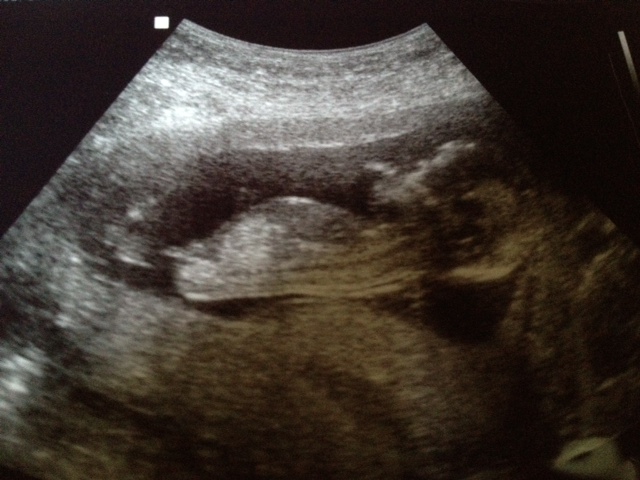

Any guesses.... Us tech said she guesses girl

first photo is showing the cord, from second photo I would say girl! :)

Thank you guys so much for responding! I have one more that I would love for you guys to look at......I found this in my stash from today and THIS one looks more boyish to me...what do you think?

Or is that part of a leg or cord or something? I'm HOPING the one at the bottom is the more reliable one :D